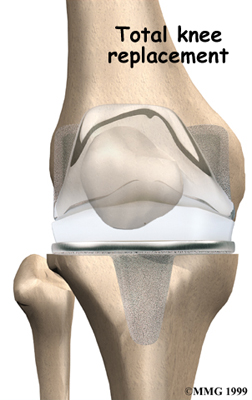

Artificial Knee Replacement

An artificial knee replacement is the ultimate solution for advanced knee OA.

Surgeons prefer not to put a new knee joint in patients younger than 60. This is because younger patients are generally more active and might put too much stress on the joint, causing it to loosen or even crack. A revision surgery to replace a damaged prosthesis is harder to do, has more possible complications, and is usually less successful than a first-time joint replacement surgery.

Related Document: FYZICAL Northeast Naples Guide to Artificial Joint Replacement of the Knee